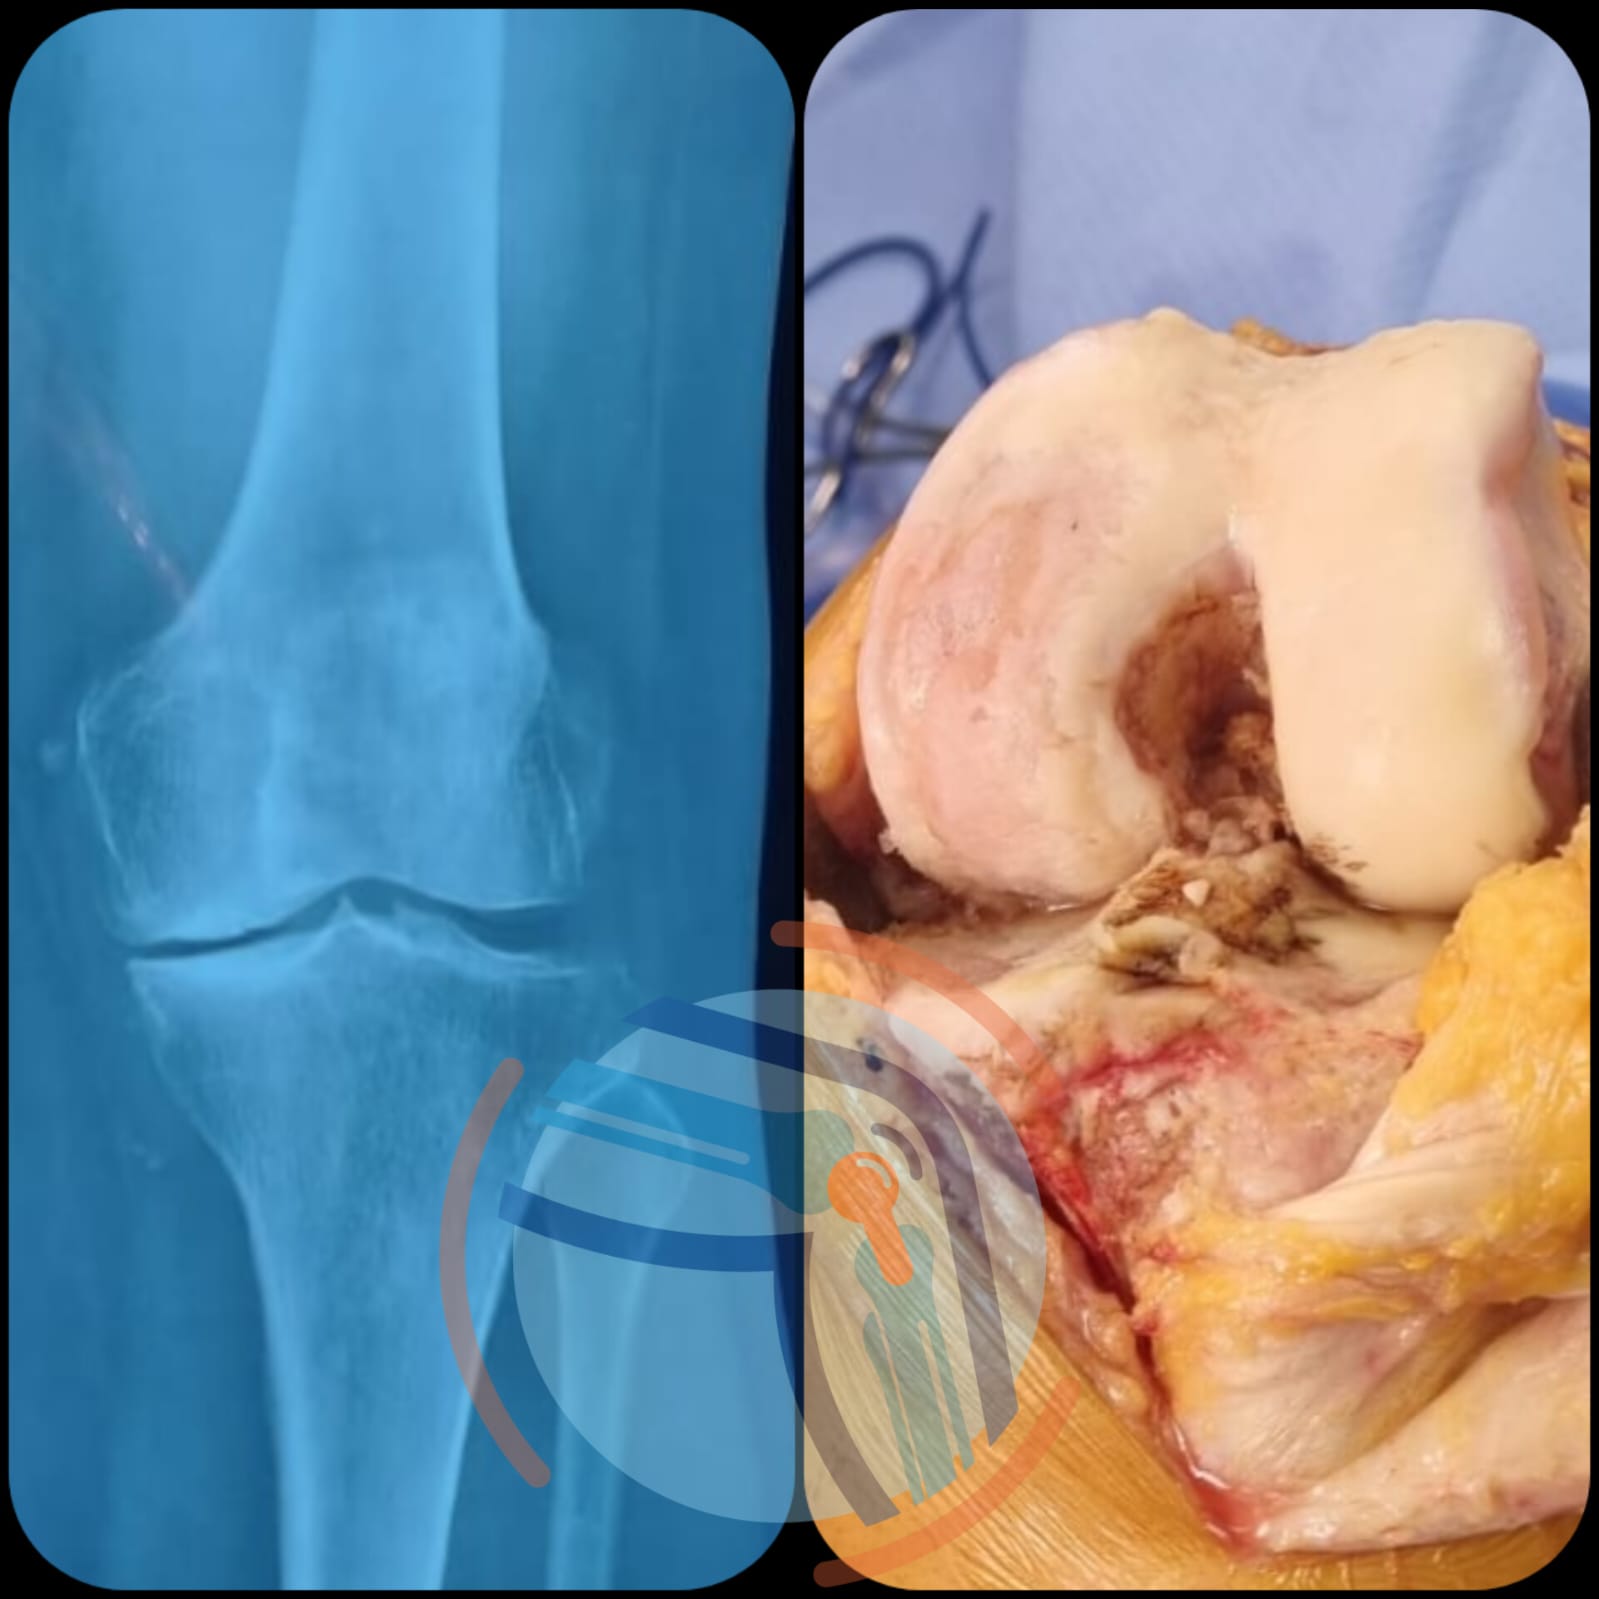

GONARTROSIS

Manejo especializado de Gonartrosis o artrosis de rodilla.

Lesiones de Ligamento cruzado

Las lesiones ligamentarias de la rodilla, pueden causar un desgaste prematuro de la articulación.

Lesiones Meniscales

Valoración especializada en lesiones de meniscos, producidas por traumatismos en las rodillas.